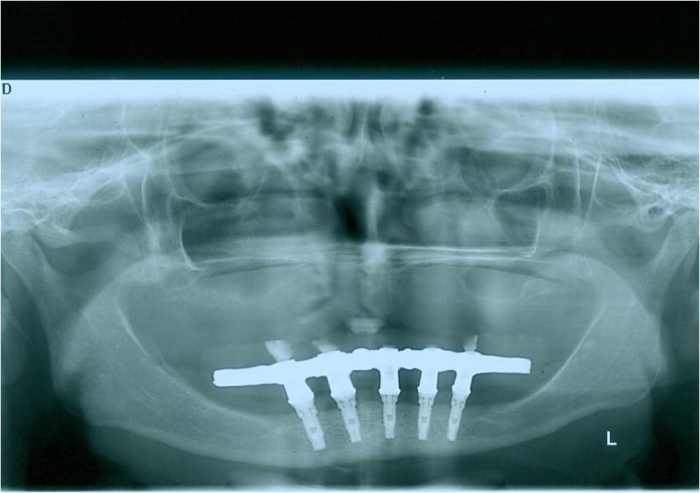

Raio x dos implantes